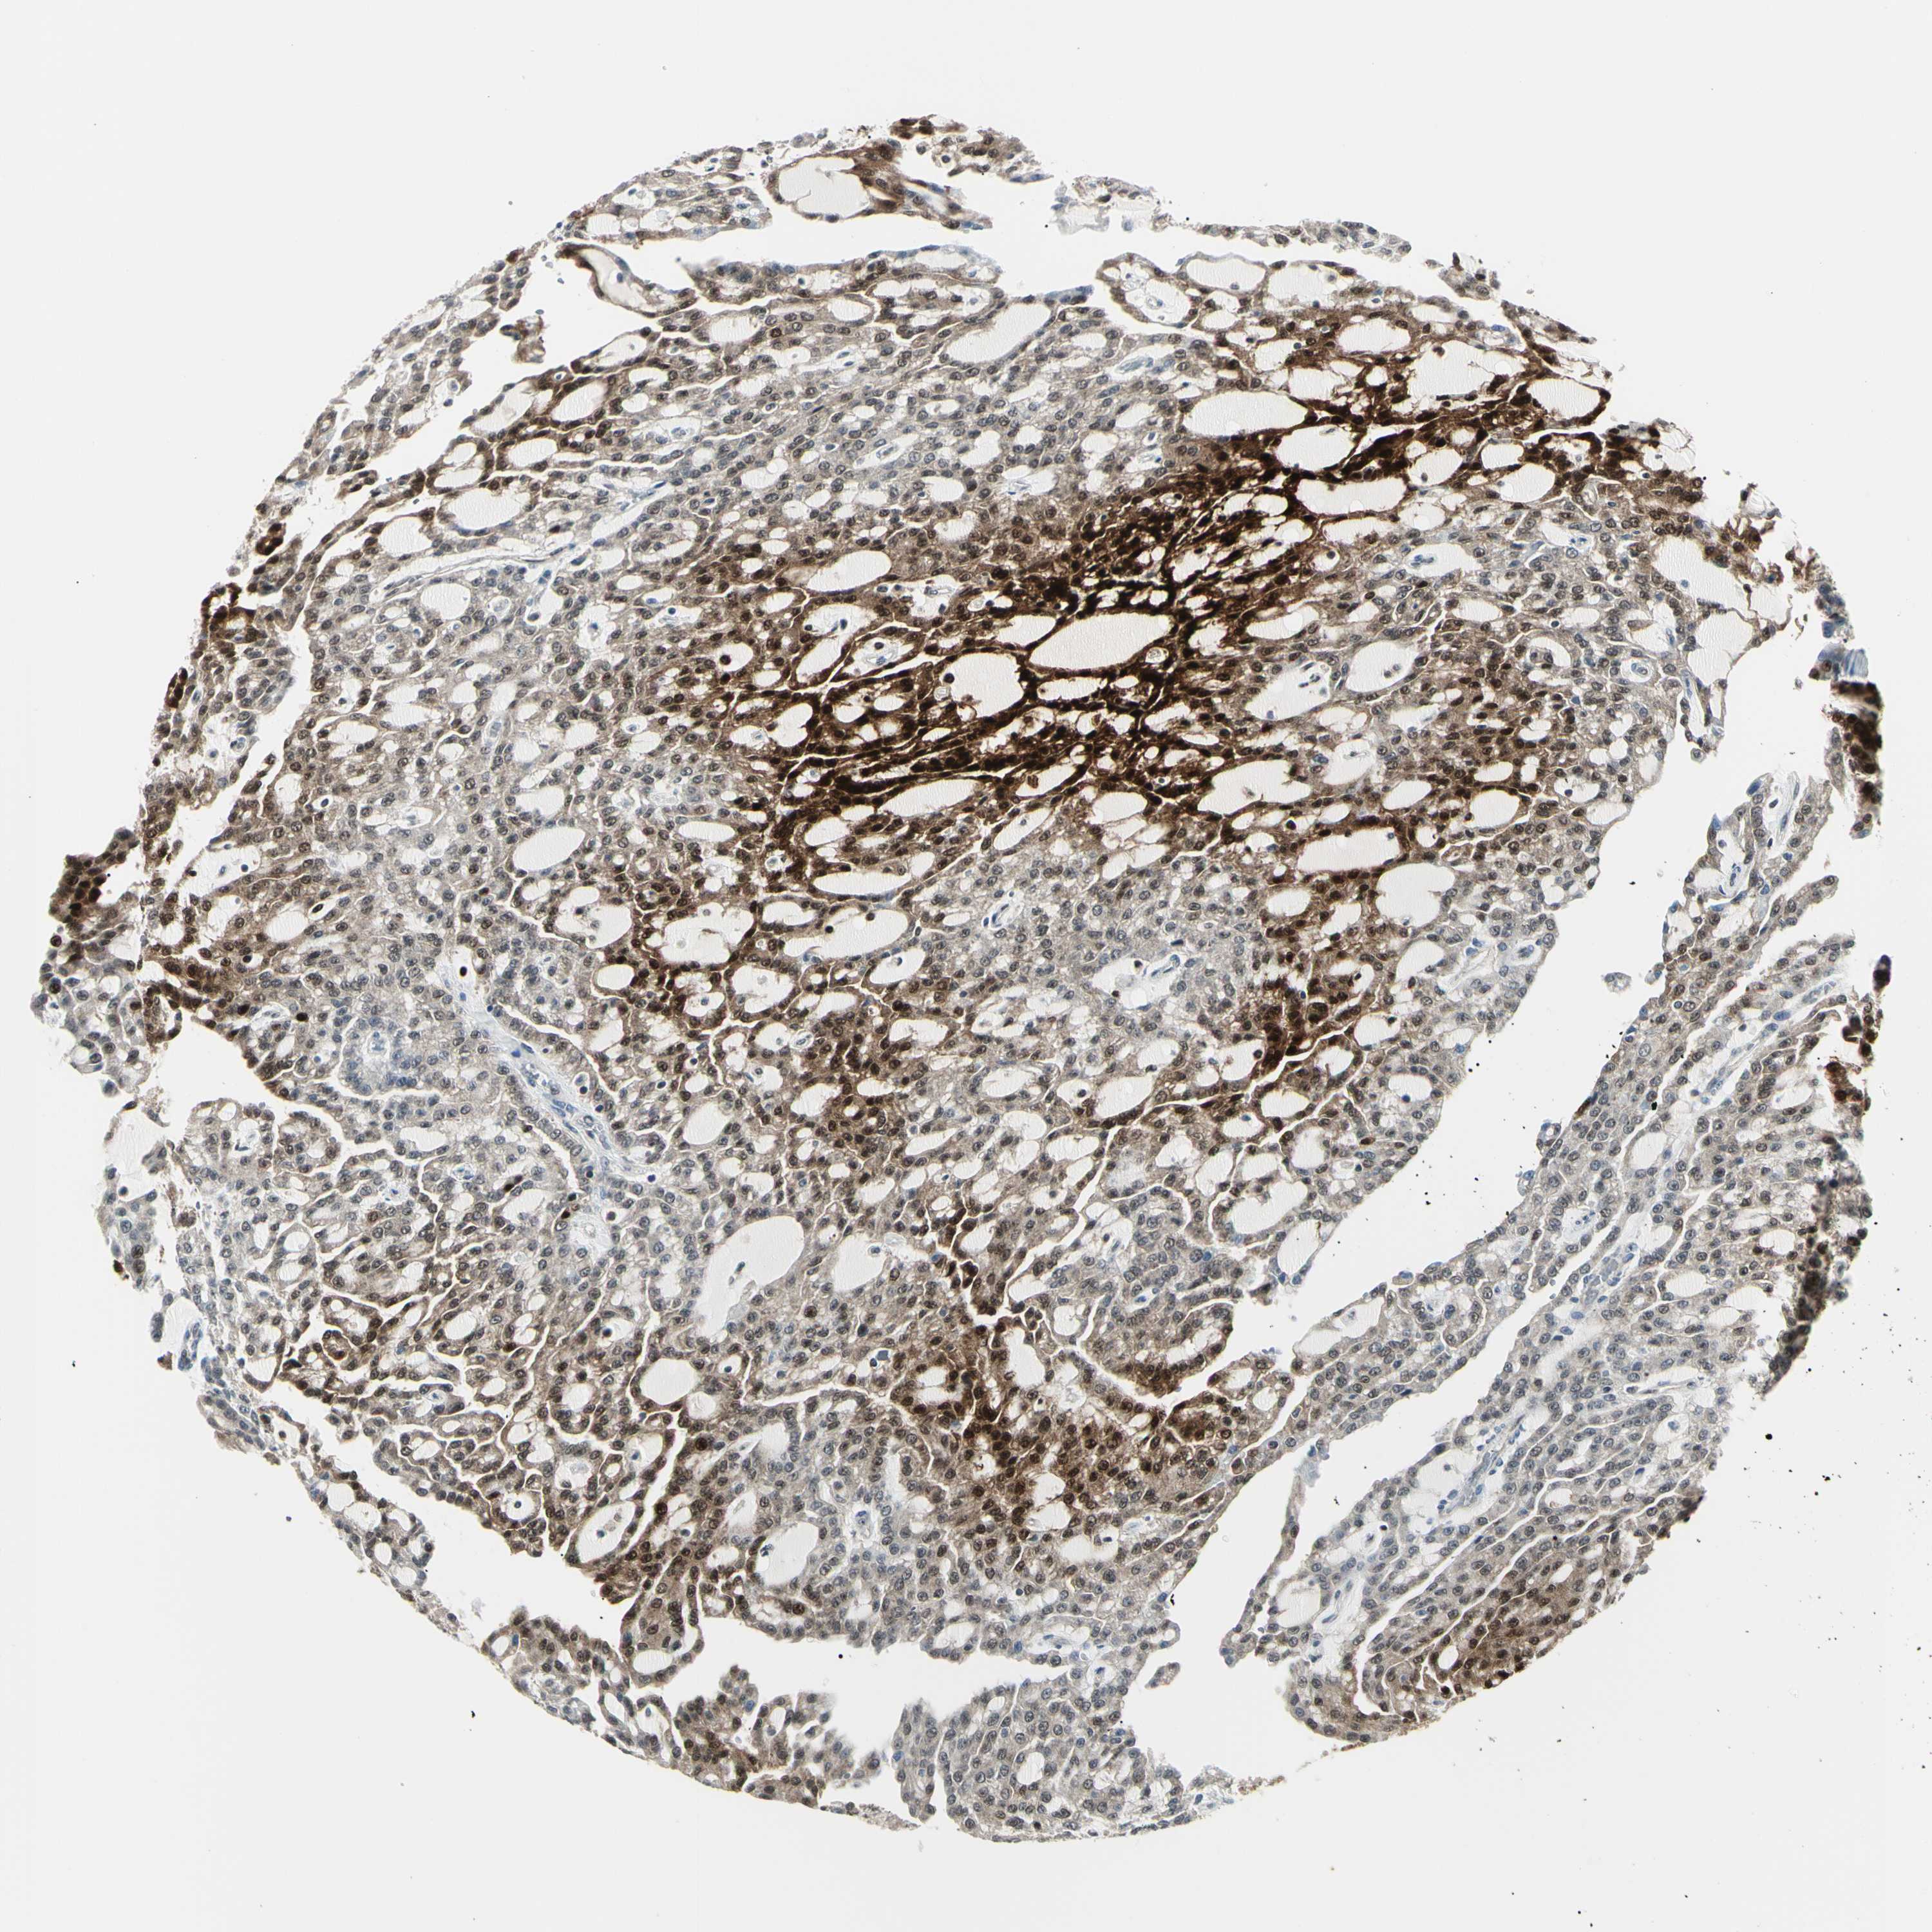

CANCER RENAL CANCER Show tissue menu

KICH TCGA KIRC TCGA KIRC VALIDATION KIRP TCGA PROTEIN RCC CPTAC PROTEIN EXPRESSION